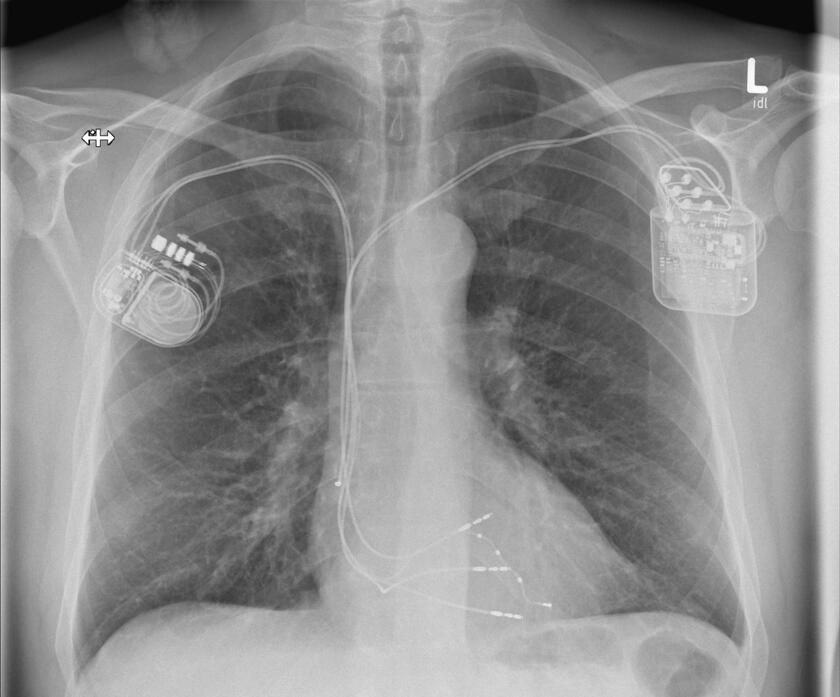

Wenn das Herz zu langsam schlägt, dann spricht man von einer Bradykardie. Diese ist meistens behandlungsbedürftig, denn sie kann zu Ohnmachtsanfällen (Synkopen) und im schlimmsten Fall zu einem Herzstillstand führen. Wenn sich keine behebbare Ursache finden lässt, ist die Implantation eines Herzschrittmachers die Therapie der Wahl. Der Schrittmacher regt den Herzmuskel mit leichten nicht spürbaren elektrischen Impulsen zum regelmäßigen Schlagen an. Der Herzschrittmacher wird in der Regel im Brustbereich unterhalb des Schlüsselbeines eingesetzt. Der kleine Eingriff erfolgt unter lokaler Betäubung während eines kurzen stationären Aufenthaltes oder auch ambulant. In unserer Klinik werden alle gängigen Systeme implantiert. Gerne informieren wir Sie in unserer Sprechstunde über weitere Einzelheiten. Hier erfolgt auf Wunsch auch die Nachsorge der implantierten Geräte (Sprechstunde).

Defibrillator

Die Implantation eines Defibrillators (ICD) erfolgt in der Regel bei einem erhöhten Risiko für gefährliche Herzrhythmusstörungen oder nach einem überlebten plötzlichen Herztod (SCD). Ein elektrischer Schock sorgt beim Auftreten einer entsprechenden Rhythmusstörung dafür, dass ein aus dem Takt geratenes Herz wieder richtig schlägt und die lebensbedrohliche Situation beendet wird. Die allermeisten Defibrillatoren haben zusätzlich die Funktion eines Herzschrittmachers. Ähnlich wie ein Herzschrittmacher wird das ICD-Gerät im Brustbereich unterhalb des Schlüsselbeines unter lokaler Betäubung eingesetzt. In unserer Klinik werden alle gängigen Systeme implantiert. Gerne informieren wir Sie in unserer Sprechstunde über weitere Einzelheiten. Hier erfolgt auf Wunsch auch die Nachsorge der implantierten Geräte (Sprechstunde).